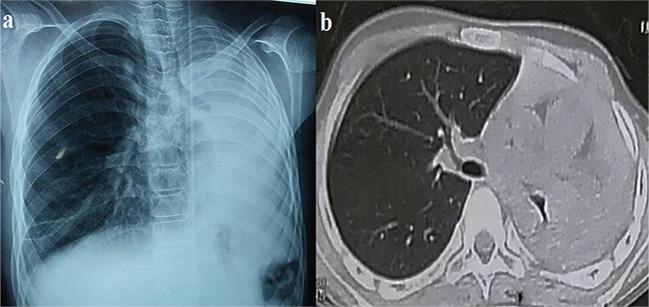

We describe a 13-year-old boy with a history of bronchial asthma and left lower lobectomy, with persistent cough and left-sided chest pain when he went to the emergency room. Chest radiography showed complete left lung opacity denoting total left lung collapse, and flexible bronchoscopy revealed cohesive casts totally occluding the left bronchus, with frequent recurrence that finally ended with left pneumonectomy.

我们描述了一名 13 岁男孩,他有支气管哮喘和左下肺叶切除术病史,因持续性咳嗽和左侧胸痛到急诊就诊。胸部 X 线摄影显示完全性左侧肺不张,提示左侧全肺塌陷,而软性支气管镜检查显示粘性铸型完全阻塞左侧支气管,频繁复发,最终导致左侧肺切除术。